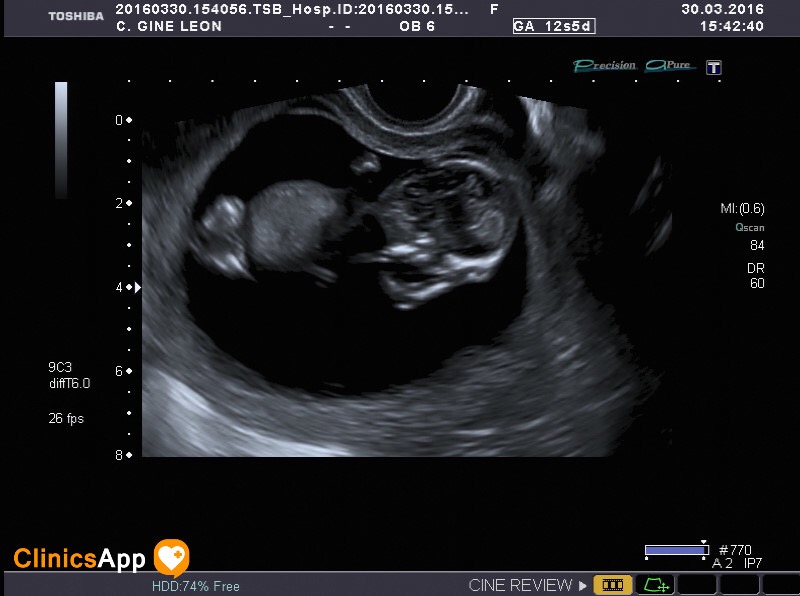

Esta es la ecografía de la Clínica San Francisco. Aquí son más enrollados y te hacen también un vídeo. Dice la ginecóloga que es posible que sea un niño pero que no está muy claro a estas alturas todavía.